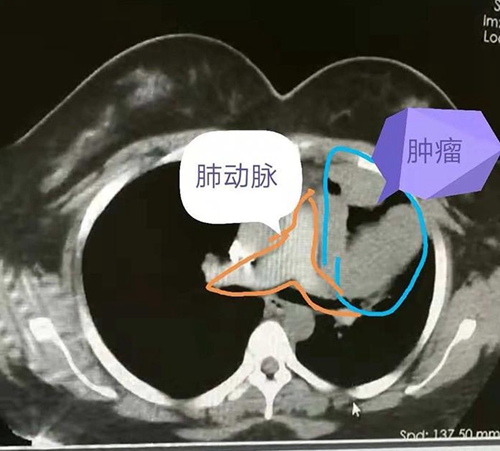

可是,女孩没有想到的是,肿瘤的生长超出预期,最近两周突然出现睁不开眼的情况。再次就医,医生告诉她,这应该是胸腺瘤生长造成的重症肌无力。再次检查,发现肿瘤较8月份明显长大, 同时发现肿瘤压迫了心脏大血管和肺组织。

从手术本身来考虑,这个手术风险很高,一是在肿瘤切除的时候可能造成大出血,下不了台;另一方面,由于肿瘤和周围脏器生长密切,不一定能完整切除。

手术中发现肿瘤侵犯了肺动脉外膜,对肺也有侵犯,经过2个多小时的仔细剥离,终于完整切除了肿瘤,同时,还切除了部分心包和受侵犯的肺组织。